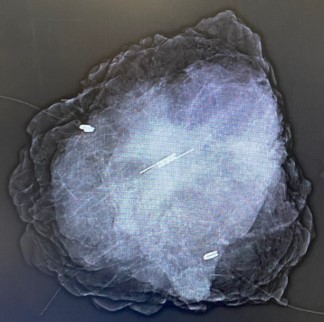

Figure 3: Intra operative mammogram for the left breast excision Specimen showing the SAVI reflector in the middle of the tissue.